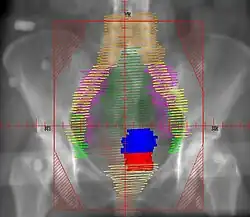

Ab dem Stadium FIGO IB2 wird zur Feststellung der Tumorausdehnung eine Kernspintomographie (MRT) empfohlen, da diese in Ergänzung zur Tastuntersuchung geeignet ist, die Größe des Tumors im kleinen Becken, die Beziehung zu den Nachbarorganen und die Eindringtiefe zu bestimmen.[4]